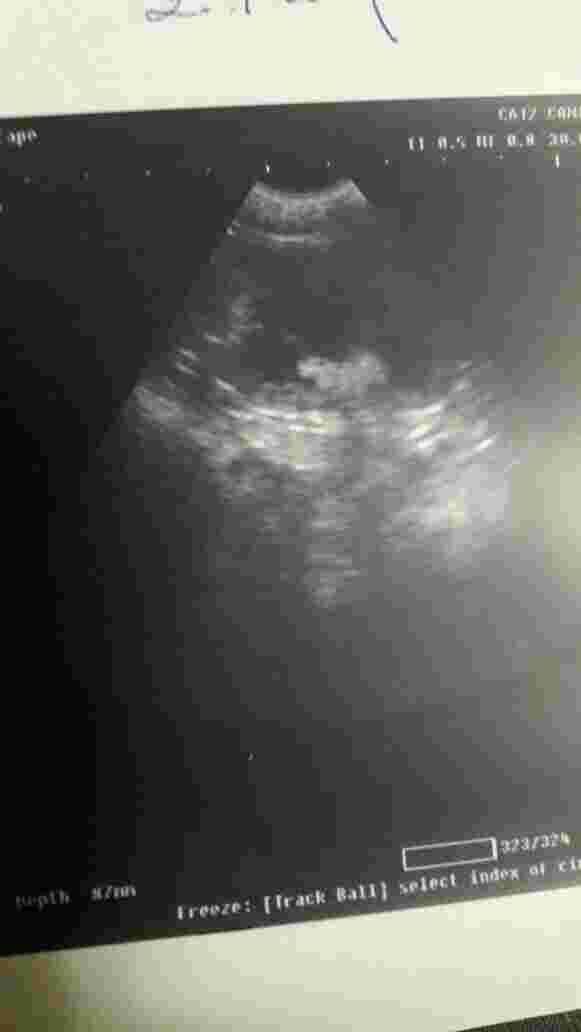

hello yesterday i went to the vet after my cat lost weight he told me that my cat suffers from kidney failure now he has one kindey that works but not with high efficiency and the other one stopped completely now my cat refuses to eat or drink what should i do and how long can he live by one kidney? a picture of his kidneys below

Kidney failure is common amongst cats and the survival time varies based on the underlying cause of the kidney failure. A full report of what was found on the ultrasound would help here; because just an image of the kidney itself isn't enough to make a diagnosis as to why the 1 kidney is no longer working nor can we predict how long he can live based on this. The only thing that can be gathered based on the photos you have sent is that there is hydronephrosis (distension of the kidney with fluid) of one of the kidney's which leads to severe malfunction . More importantly, since your cat is refusing to eat, he needs to be hospitalized and given IV fluids, force feeding (by means of a tube if necessary) and pain medication. He will not be able to survive long if he does not eat. Once he is able to be stabilized (by eating on his own), then you can try to manage his condition at home with subcutaneous fluids and a prescription kidney diet (i.e. Hill's K/D, Royal Canin renal). However, the condition that he has is severe and survival is going to be tough for him, especially since one of his kidney's is in such bad shape. I send all my best to both you and your cat. I hope he gets better soon. Take care.